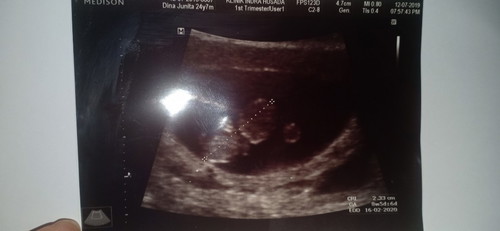

usia kandungan 8week, Alhamdulillah sudah ada janin nya ? Katanya orang orang normal panjang janin 8 minggu 4cm , ini janin ku 2,33cm tapi kata dokter normal kok dan aku tetap bersyukur semoga selalu diberi kesehatan dan kelancaran sampai menuju kelahiran ya nak??

Saya juga baru usg bun, usia kandungan saya hari ini tepatnya 8w3d panjang janinnya 20,3

2.3cm maksudnya hehe